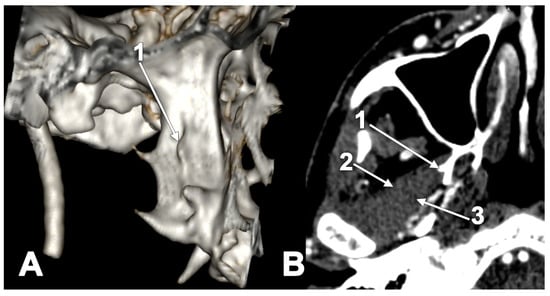

The Accessory Pterygoid Fovea

- Rusu, M.C.; Dinca, D. Accessory pterygoid fovea of the human mandibular condyle. Cranio 2021, 39, 452–456. [Google Scholar] [CrossRef] [PubMed]